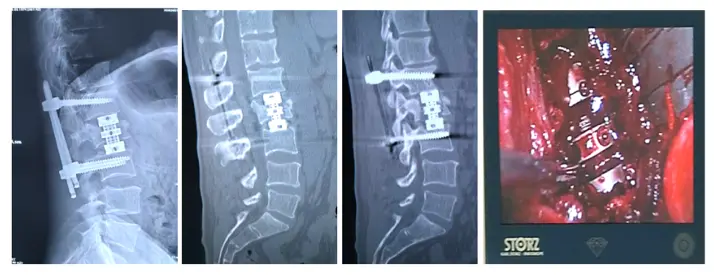

Компрессионно-оскольчатый перелом второго поясничного позвонка. Циркулярный спондилодез 360 градусов с видеоэндоскопической ассистенцией.